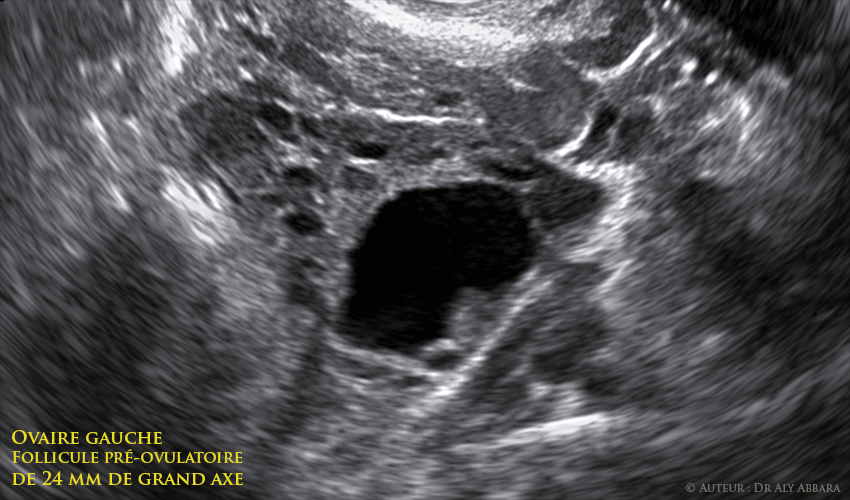

Ovaire gauche - follicule de Gaaf mature

Utérus : la contractilité utérine et l'aspect échographique de l'endomètre à la fin de la phase proliférative, avec ovaire gauche contenant un follicule de De Graaf mature (pré-ovulatoire) de 24 mm de grand axe :

Échographie réalisée au 13e jour du cycle menstruel - glaire pré-ovulatoire - endomètre de 11 mm d'épaisseur.